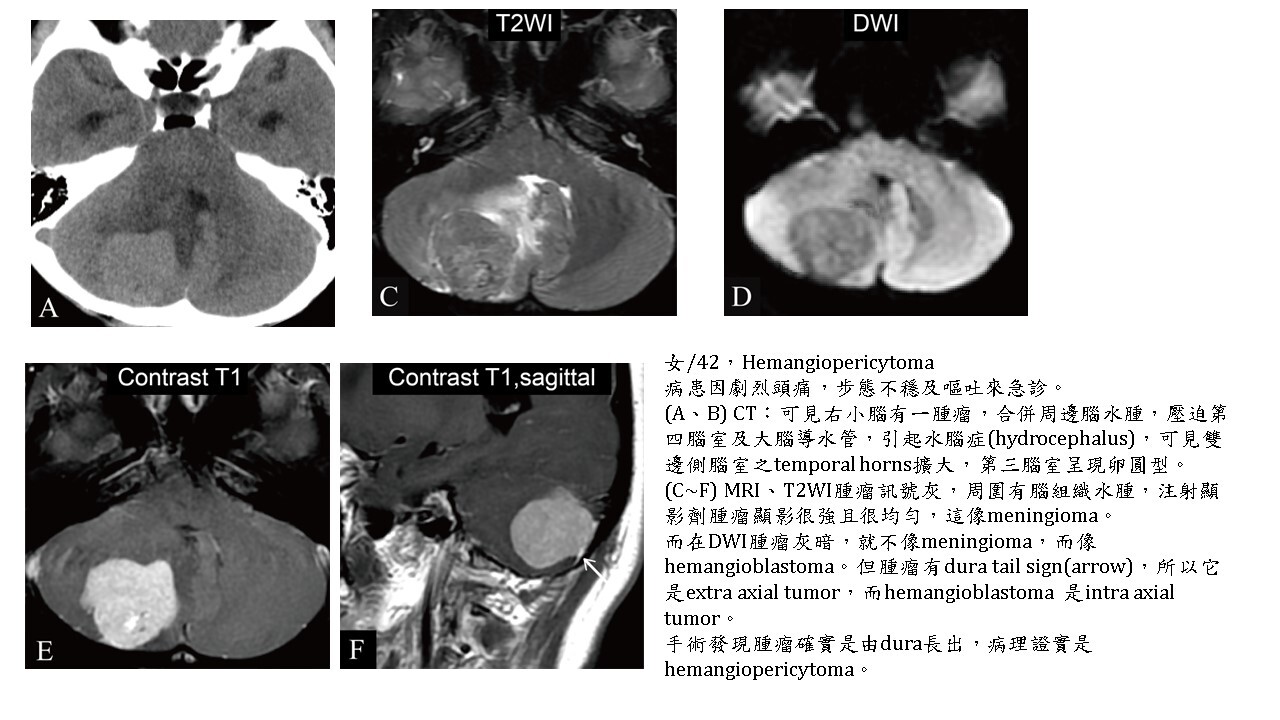

大多數的腫瘤(brain tumors)的實體部分(solid part),不管良性及惡性,DWI都會稍白,但對於血管豐富的hemangioblastoma, hemangiopericytoma則DWI暗。